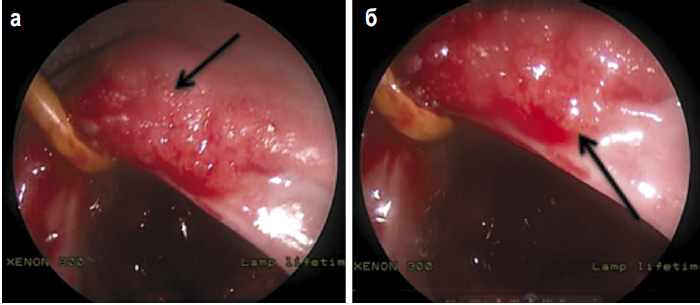

В связи с подозрением на рецидив РН и папилломатозом мягкого неба решено провести биопсию тканей носоглотки и небных миндалин, а также выполнить удаление папиллом ротоглотки. Проведено эндоскопическое эндоназальное хирургическое вмешательство. Под контролем жесткого эндоскопа Хопкинса 0°, 4 мм визуализирована рубцовая ткань в своде носоглотки. Удалены выбухающие ткани на участке 1,5 см, взята биопсия небных миндалин. Гемостаз. В области мягкого неба визуализированы сосочковые разрастания розового цвета, которые не кровоточат (рис. 4). Произведены плоскостная резекция мягкого неба слева на участке 1,5×2 см, удаление папиллом. Гемостаз. Материал направлен на гистологическое исследование.

Рис. 4. Множественные папилломы мягкого неба.

Fig. 4. Multiple papillomas of the soft palate.